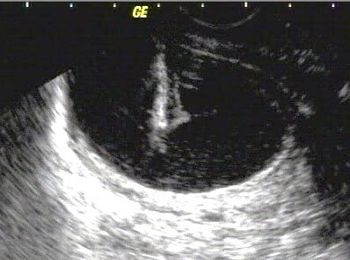

This is a confirmed case of scar ectopic pregnancy. Yesterday, I carried out this exam in an emergency room, without much time to perform an adequate sonogram, the patient did not feel good with “cramps” but no signs of bleeding.